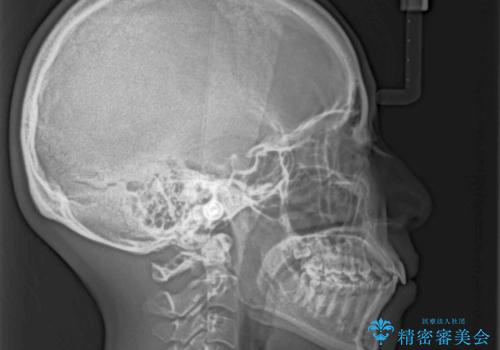

- 出っ歯で唇が閉じにくいとのことで来院された患者様です。

顎先に力を入れないと唇が閉じきれない口元であったので、上下左右の第一小臼歯4本を抜歯して、ワイヤー装置にて矯正治療を行うこととしました。